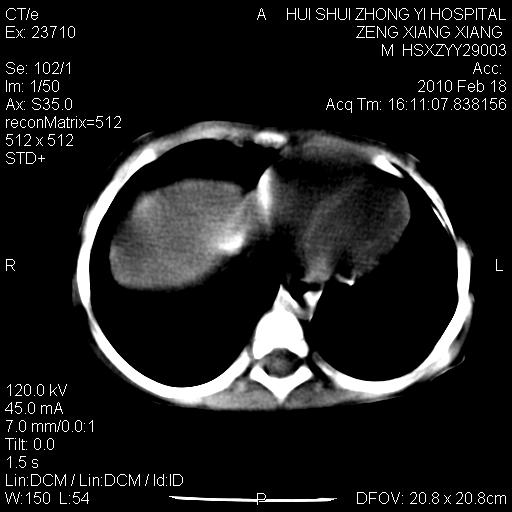

标题: PED3106:男,2岁,腹胀1月。 [打印本页]

标题: PED3106:男,2岁,腹胀1月。

定位腹膜后,肾上腺来源;

定性:恶性神经源性,肾上腺神经节母细胞瘤可能性大。

鉴别:肝母、肾母、肝脏中胚层错构瘤。

依据:年龄、有钙化,肾脏及肝脏受压移位。

肝母细胞瘤可能性大,右肾形态大体可见,不支持肾母细胞瘤,右肾移位不明显,肾上腺神经母细胞瘤可能性不大。